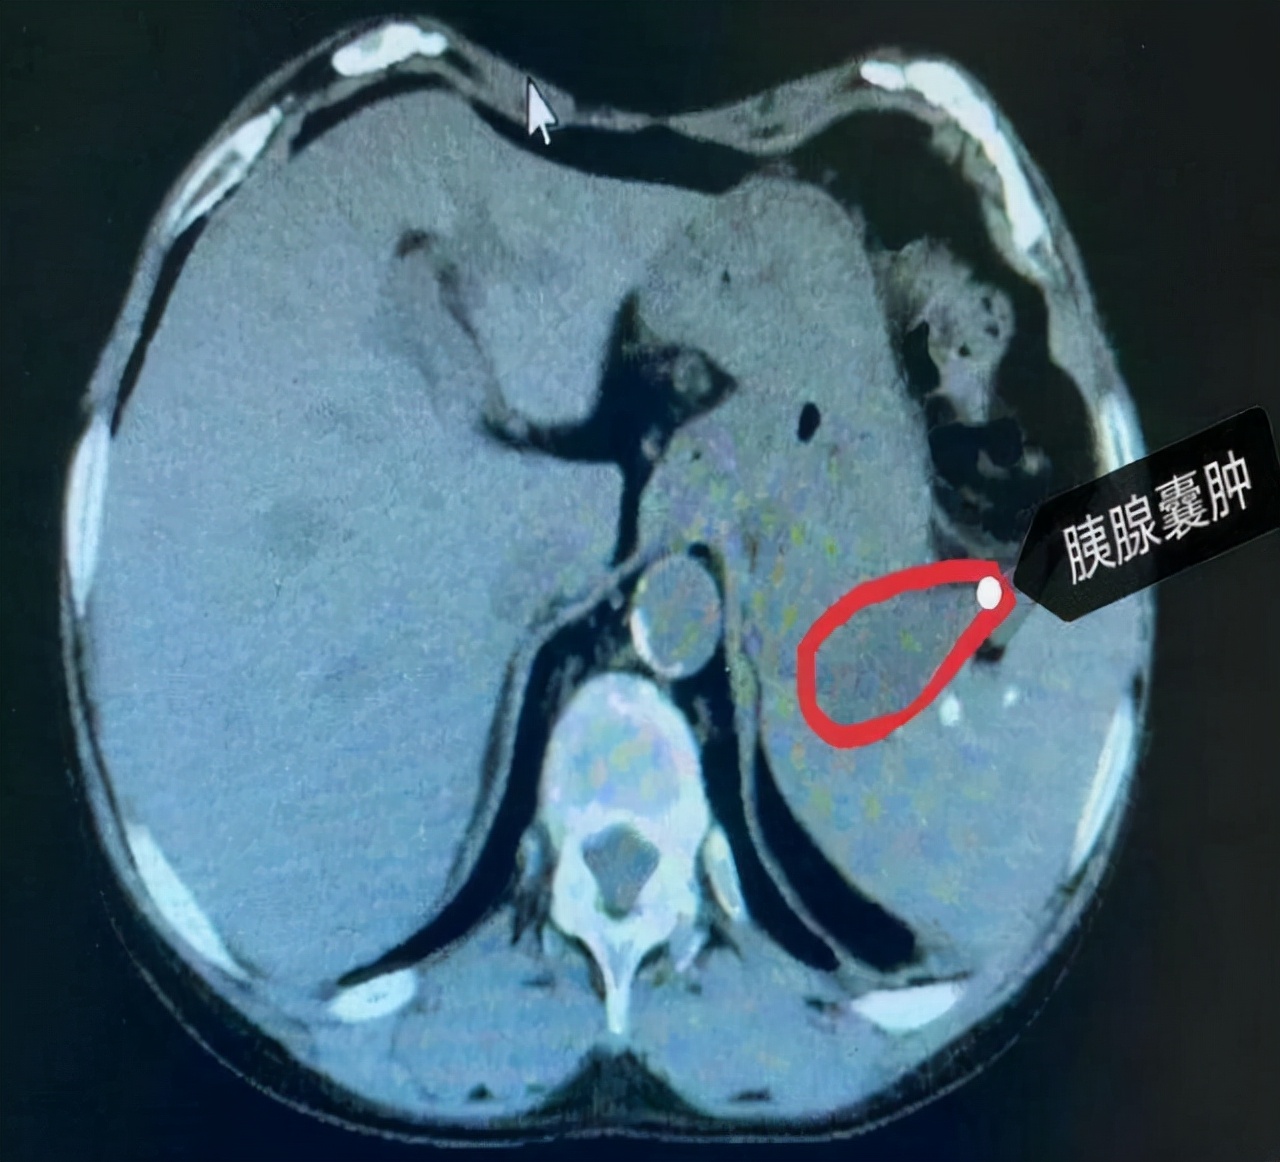

胰腺囊肿

胰腺囊肿有真性囊肿和假性囊肿两种,其中假性囊肿最常见,真性囊肿少见,如果胰腺囊肿是真性囊肿,胰腺的囊肿比较小,不需要治疗,定期观察就够了,每年至少检查一次b超,但胰腺假性囊肿必须治疗,特别是较大的囊肿必须积极治疗。

感染发生在囊肿内部,如果严重感染会发展成脓肿,患者会出现严重的腹痛症状,甚至导致败血症,由于胰腺囊肿急剧增大,囊肿刺入胃肠道,少数患者会出现大出血,严重者可能导致死亡。

胰腺囊肿非常容易压迫到患者的邻近器官,从而引起黄疸等症状,如果囊肿压迫到胰管,胰液的排出会受到阻碍,大的囊肿会压迫到胃肠道,造成食物通过时的障碍。

当囊肿与胸腹腔形成瘘管时,会促使患者出现胰性腹水和胸水的症状,被感染的囊肿容易破裂进入腹腔,形成弥漫性腹膜炎,严重时可危及患者生命。